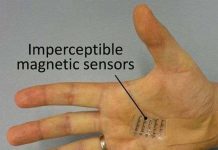

Coleman đang tìm cách để ghi lại các tín hiệu não và tín hiệu cơ điện tử, trong một cách không làm hạn chế khả năng của đối tượng để di chuyển trong một khung cảnh tự nhiên, khi tình cờ nghe bài thuyết trình của giáo sư John Rogers, Đại học Illinois, Hoa Kỳ, người đã phát triển thiết bị điện tử linh hoạt trên. Hiện nay, các tín hiệu điện từ não bộ và cơ xương được thu thập thông qua Phép ghi điện não đồ (EEG) và phép ghi cơ điện (EMG), tương ứng. Chẩn đoán EEG và EMG liên quan đến việc gắn các điện cực bằng nhựa để cơ thể với chất kết dính hoặc kẹp, áp dụng một loại gel dẫn và gắn tất cả các hộp của bảng mạch, nguồn điện và các thiết bị thông tin liên lạc. Nhóm nghiên cứu cho thấy một mảng rộng của các thiết bị điện tử, bao gồm cảm biến, các bóng bán dẫn, các nguồn cung cấp năng lượng như các tế bào năng lượng mặt trời và các ăng-ten không dây, có thể được kết hợp trên một thiết bị duy nhất và gần như không gây chú ý cho người sử dụng.

Ngoài giáo sư John Rogers, đã tạo khả năng chính của công nghệ với chuyên môn của mình trong ngành điện tử, dự án đã được dẫn dắt bởi Yonggang Huang, giáo sư kỹ thuật cơ khí, đã tối ưu hóa các đặc tính cơ học của thiết bị. Cuối cùng là giáo sư Coleman sẽ giúp xác định và chứng minh tiện ích của thiết bị trong các ứng dụng y sinh. Nhóm nghiên cứu của Coleman, với nền tảng kết hợp trong kỹ thuật điện tử và khoa học thần kinh, giúp thiết kế các mạch điện hoạt động hiệu quả để kết nối giữa các thiết bị và sóng não mà không cần sử dụng chất gel dẫn điện, và theo các cách thức xử lý tín hiệu thống kê cần thiết đáng tin cậy để có được các tín hiệu thần kinh từ não bộ hoặc các cơ bắp thông qua thiết bị của giáo sư John Rogers.

Nhóm nghiên cứu của giáo sư Coleman đã sử dụng các thiết bị để cho phép một người nào đó có thể kiểm soát một trò chơi máy tính bằng các cơ trong cổ họng của mình bằng cách nói các lệnh. Về nguyên tắc, các chức năng tương tự có thể đạt được bằng cách chỉ đơn giản là ra lệnh bằng lời nói chứ không cần phải là nói to. Điều này đã được thực hiện bằng cách áp dụng một thuật toán nhận dạng mô hình triển khai thực hiện theo nhóm của giáo sư Coleman, và của dữ liệu được lấy từ một phép ghi cơ điện (EMG) trong cổ họng. Giờ đây khả năng trên đã được chứng minh, bước tiếp theo là tích hợp tất cả các thành phần vào một thiết bị duy nhất. Giáo sư Coleman tin rằng các thiết bị hỗ trợ cho việc chăm sóc sức khỏe là quan trọng tại một thời điểm hiện tại khi mà người ta đang sống lâu hơn nhưng hay mắc phải các vấn đề thần kinh như bệnh Parkinson và chứng mất trí nhớ.